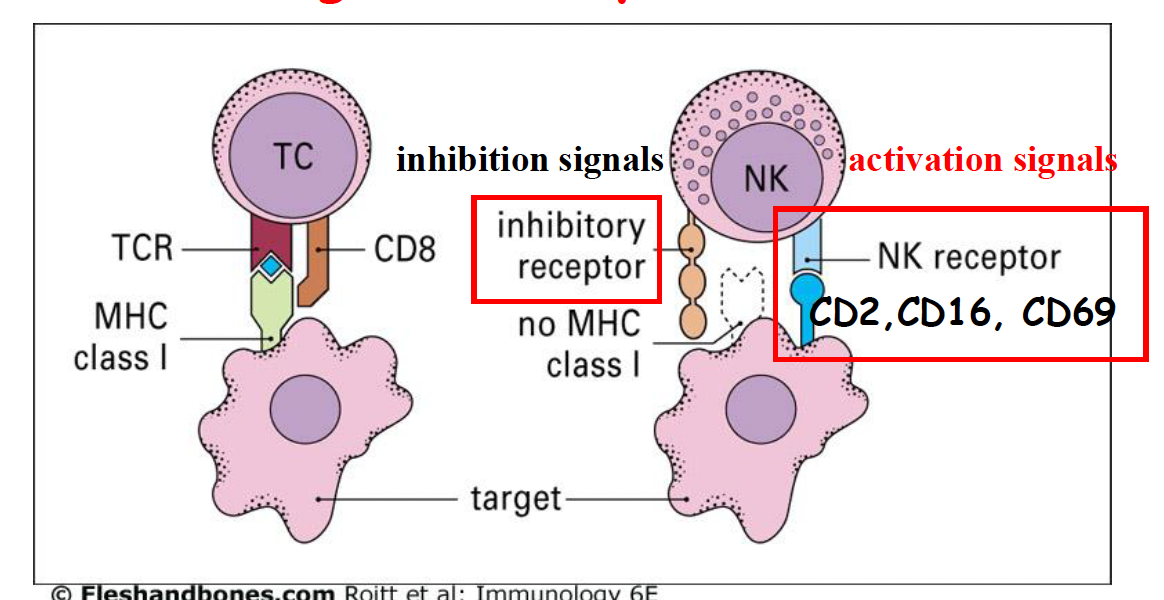

NK cell

-

NK 細胞佔了血液和脾臟淋巴細胞的 5~20%

- 血液中: CD16

-

抓 MHC I 不表現的

- NK receptor 傳遞殺了我

- NK receptor 傳遞殺了我

-

NKG2D

- 辨識 MHC Ib

-

先天性免疫

- 被刺激:IL-12、IL-15、IL-18、IFN-α

- 分泌: IFN-γ

-

IgGr

- 攻擊免疫複合體

NK cell inhibitory receptor

- CD94 認 HLA-E

- KIR 認 MHC Ia (HLA-A, B, C)

- ITIM 傳遞抑制訊息

- K

- lysine

Info

- ITIM

- immunoreceptor tyrosine inhibitory motif

- HLA E

- human leukocyte antigen E,一種 MHC I ,一般的MHC I 呈現抗原,HLA E 呈現製造 MHC I 剩下的垃圾。

如何殺

- Fas ligang

- 認細胞的 Fas (CD95),導致凋亡

- 有毒的 Cytokines

- tumor necrosis factor (TNF)

- lymphotoxin (LT)

- Granules

- 先 Perforin 穿孔,再送granzymes導致凋亡